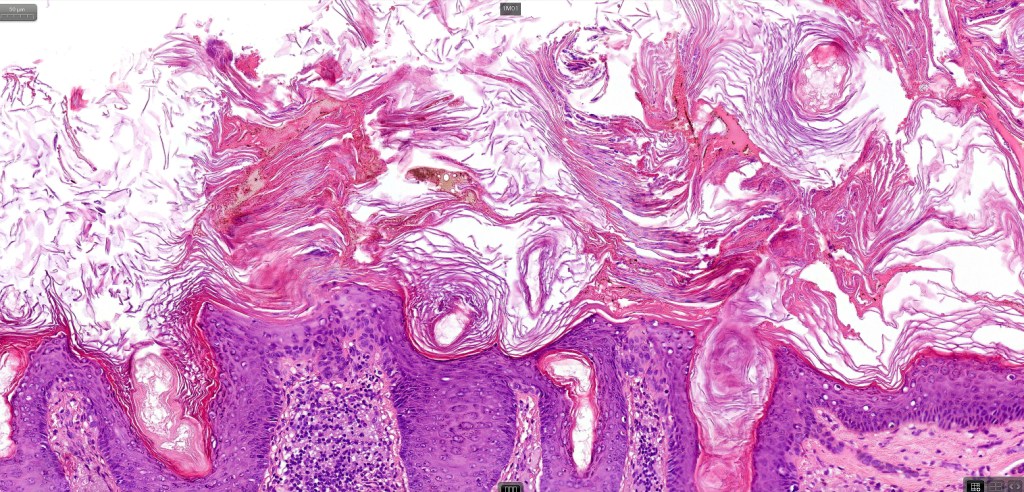

•Hyperkeratotic/hyperplastic actinic keratosis represents the prototype-alternating hyperkeratosis & parakeratosis- the former overlies the follicular & sweat duct ostia (Freudenthal funnel) while the latter overlies the interadnexal dysplastic epithelium & ranges from basal cell layer though to full thickness dysplasia (Bowenoid actinic keratosis); budding from the epidermis is a common finding; dysplastic epithelium commonly forms a mantle around the follicles and superficial sweat ducts

•Solar elastosis